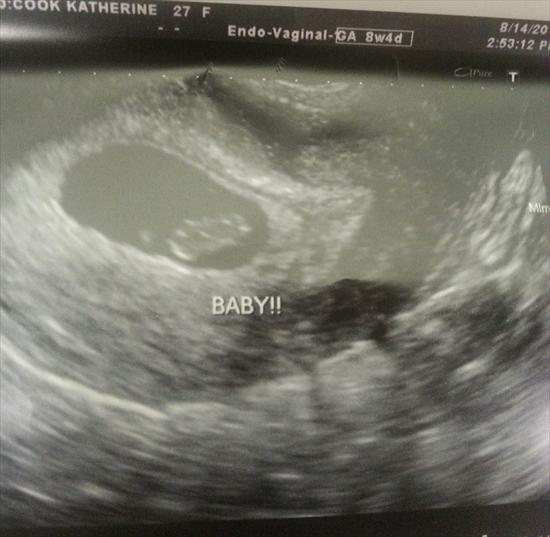

this one is the vaginal scan same day 7 weeks 3 days

Attachment 20401